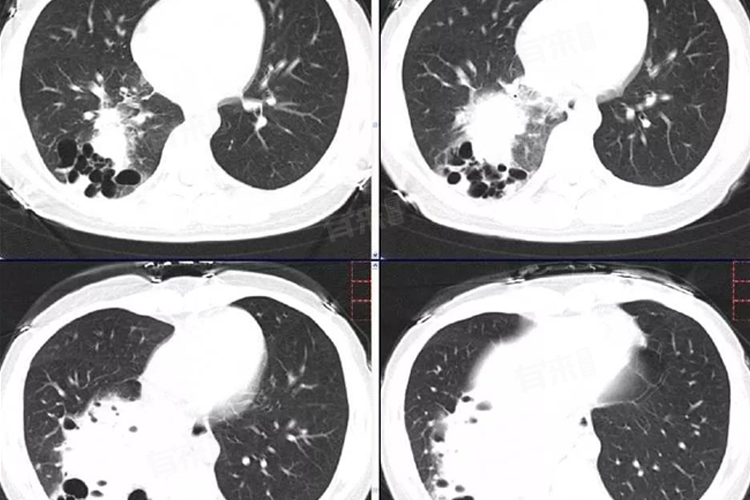

在预防和治疗胎儿隔离肺时,需要综合考虑此类因素,制定针对性的措施。定期进行产前检查是发现胎儿隔离肺的重要手段。通过B超、羊水穿刺等检查手段,可以监测胎儿的生长发育情况,及时发现并处理隔离肺等问题。